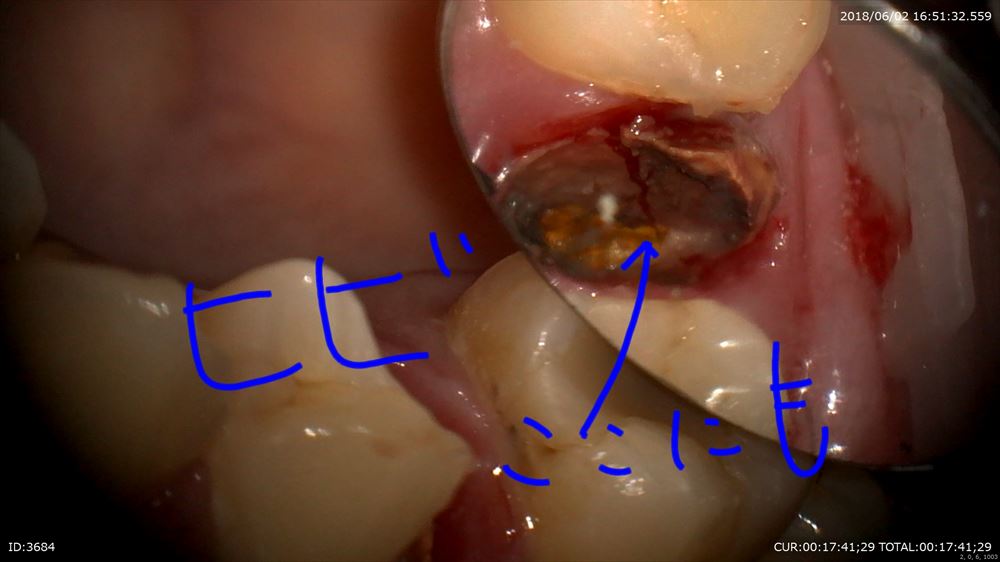

揺れている原因は

このように

歯根ごと折れて

2本ヒビがはいっています。

患者さまはこの画像をみて自分から

「ダメですね」とおっしゃっていました。

抜歯宣告を受けても納得していない方がほとんどです。その際しっかり動画で見て頂く。これ以外方法はないと思っています。抜歯も無痛で行い縫合。無痛がすべて。